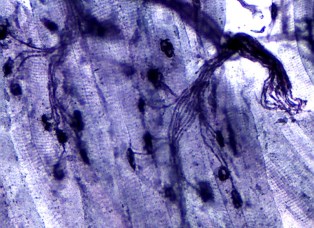

Muscles are made for producing force. Here we study how much, how fast and for how long muscles can produce force. We are studying the subtle adjustments that occur within muscles when they contract, and how they are coordinated together to produce effective movements.